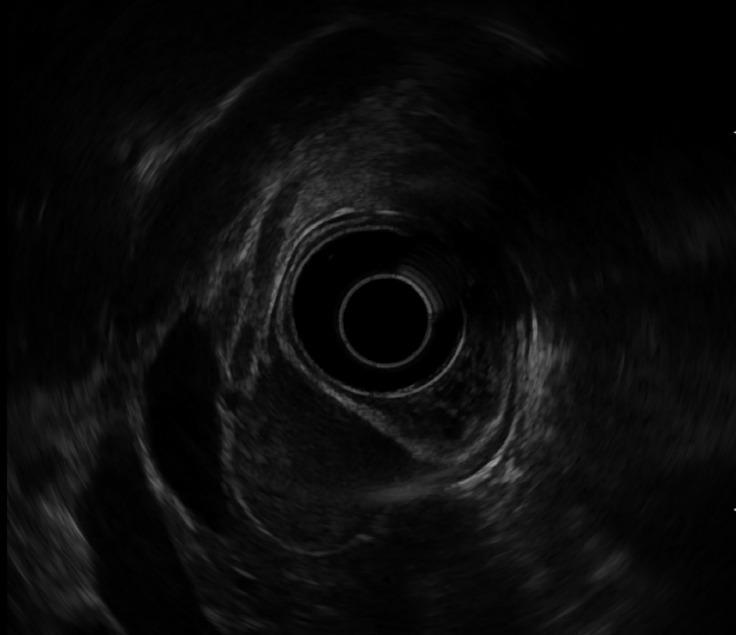

1型神经纤维瘤病(NF1)是一种多系统遗传疾病,主要影响皮肤和神经系统,导致特征性皮肤变化和良性或恶性肿瘤的发展,具有广泛的严重程度和并发症。胃肠道间质瘤是NF1患者中最常见的非神经系统肿瘤。这些肿瘤的临床、遗传和病理特征与散发性gist有很大不同。很少有其他胃肠道恶性肿瘤,如小肠腺癌、神经内分泌肿瘤和胃腺癌发生在NF1患者中。在此,我们报告一例多发性十二指肠胃肠道间质瘤合并早期胃癌的NF1患者。

Neurofibromatosis type 1 (NF1) is a multisystem genetic disorder that primarily affects the skin and nervous system, leading to characteristic skin changes and the development of benign or malignant tumors with a broad spectrum of severity and complications. Gastrointestinal stromal tumors (GISTs) are the most common non-neurological tumors occurring in patients with NF1. The clinical, genetic, and pathological features of these tumors differ significantly from those of sporadic GISTs. Very rarely, other gastrointestinal malignancies, such as small bowel adenocarcinomas, neuroendocrine tumors, and gastric adenocarcinomas, have occurred in patients with NF1. Here, we report a case of multiple duodenal GISTs and early gastric cancer in a patient with NF1.